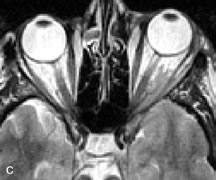

INTRAOCULAR TUMORS

On MRI, uveal melanomas have a typical appearance that helps to differentiate them from other primary and secondary intraocular tumors as well as choroidal detachments. Pigmented melanomas are hyperintense on Tl-weighted images, hypointense on T2-weighted studies, and hyperintense on proton density–weighted examinations (Fig. 24).30,31,50,80–82 These signal characteristics have been attributed to the paramagnetic properties of melanin because of stable free radicals that shorten the T1 and T2 relaxation times. Moderate enhancement is seen on postgadolinium T2-weighted images. Gadolinium-enhanced T1-weighted images are particularly sensitive in detecting choroidal melanomas.83 MRI may be less sensitive in detecting extrascleral extension of tumor than echography performed by an experienced ultrasonographer.84

Fig. 24. A. T1- and (B) T2-weighted MR scans demonstrate a small nodular intraocular mass (arrows) that is very hyperintense on the T1-weighted scan and hypointense on the T2-weighted image. This signal intensity pattern is due to the presence of free radicals within melanin granules. C and D. Postcontrast fat-suppressed T1-weighted scans demonstrate homogeneous intense enhancement of the lesion and no evidence of seleral penetration or optic nerve invasion.

Tumors metastatic to the choroid are hyperintense on T1- and T2-weighted images.24 The signal characteristics, however, may be similar to those seen with choroidal melanoma. Choroidal hemangiomas, on the other hand, have an intermediate signal on T1-weighted sequences and become hyperintense on T2-weighted images50 as well as proton density–weighted images.81